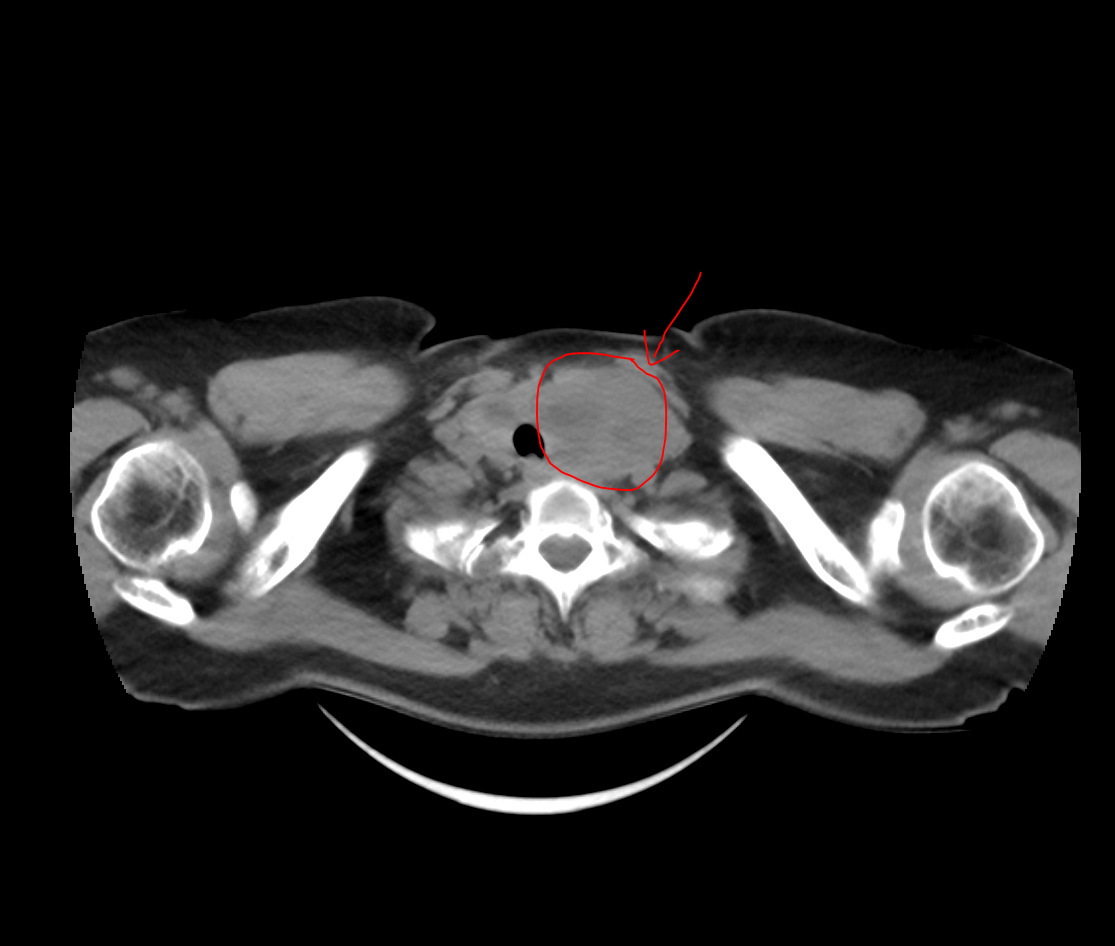

患者为中年女性,2年前因体检发现双侧甲状腺结节,当时未在意,未诊治。近半年以来,肿物大小不断增加,入院时,肿物呈鸡蛋大小并伴随吞咽不适及轻度呼吸困难症状,已成为一枚“定时炸弹”,如不及时处理,随时可能危害患者的生命安全。张军主任为患者进行详细检查,甲状腺彩超及颈部CT提示左侧较大甲状腺肿物大小约7*4cm,右侧甲状腺肿物大小约3*2cm,且左侧肿物下极位于胸骨后,压迫气管,周围毗邻重要神经、血管,建议患者尽早行手术治疗。

为保证手术安全,张军主任团队联合麻醉科、胸外科、影像科进行多学科会诊(MDT),为患者制定了周密的手术方案。术中见患者甲状腺肿物与周围组织粘连严重,团队凭借精湛的技术逐渐分离粘连,将肿瘤及其周围的血管、器官一一剥离。团队历时2小时,成功完整切除肿物,左侧肿物大小为7*5*4cm,右侧肿物大小为3*2*2cm。术后病理回报为结节性甲状腺肿伴囊性病变。